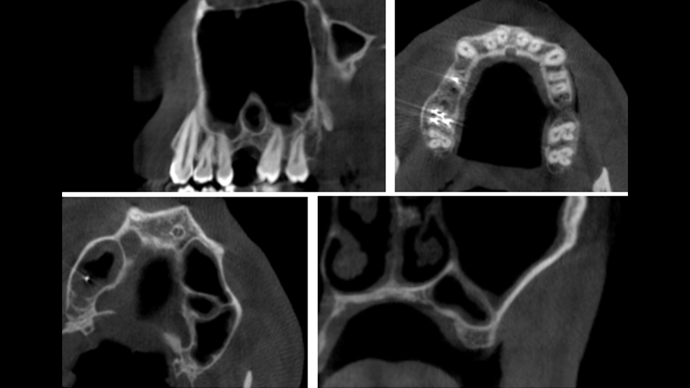

Clinical case: Ridge splitting technique using SmarThor + AnyRidge as expander

- Courtesy of Dr.Kwang-Bum Park, Korea -